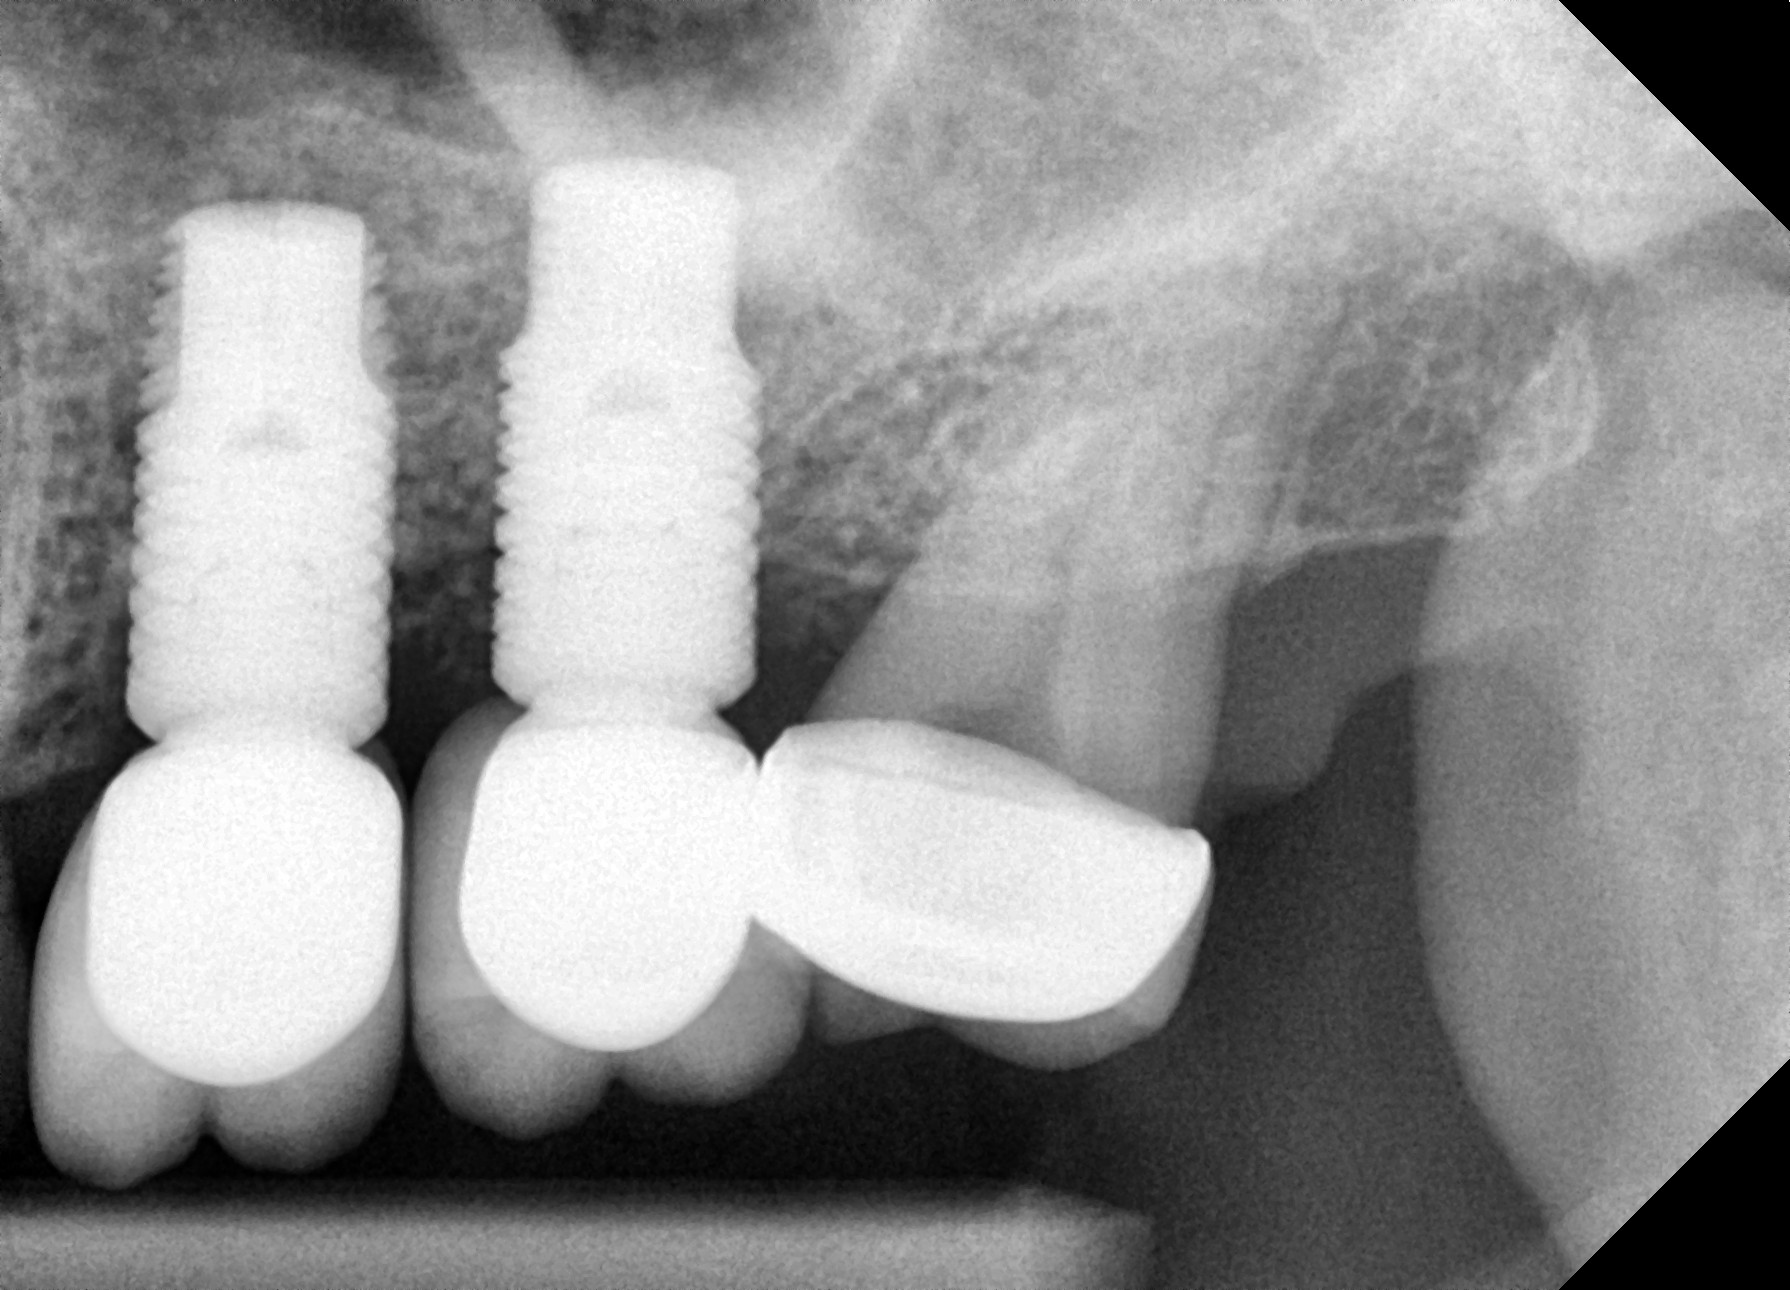

Orthodontic Treatment X-ray - After